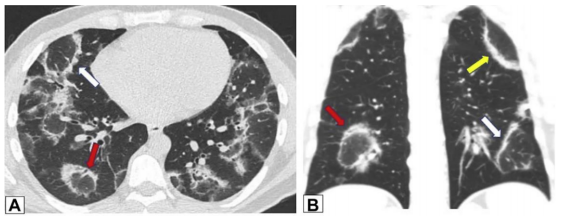

图源:Chest, 2022, 162(1):156-178.其他表现还包括小叶周围增厚和具有反晕外观特征的病变(环礁征)。图15所示为一名慢性持续性咳嗽和劳力性呼吸困难1年、体重减轻的32岁男性患者的CT图像,双侧中心磨玻璃样病灶完全被周围致密实变所包围,即反晕征或环礁征(A、B中红色箭头)。也存在不完全晕征(A、B中白色箭头)和小叶周围增厚(B中黄色箭头)。肺活检结果证实为OP。图源:Chest, 2022, 162(1):156-178.当以线性或网状为主的OP进一步发展,在周围实变或磨玻璃影后,基底和胸膜下网状形成,提示间质纤维化的发展。图16为一名73岁男性患者在呼吸困难发作4 d后获得的CT图像,分别在隆突水平(A,C)和以及肺基底水平(B,D)获得胸部CT图像。2019年的增强图像(A和B)显示双侧广泛的磨玻璃影;2021年的图像(C和D)显示磨玻璃影程度改善,但出现网状和牵拉性支气管扩张或细支气管扩张,这一模式与纤维化相符。右肺上、中、下叶的楔形活检结果显示OP。图源:Chest, 2022, 162(1):156-178.OP可导致广泛的双基底牵引性支气管扩张,其结果与非特异性间质性肺炎(NSIP)相似,并经常重叠。图17为51岁女性皮肌炎患者CT平扫图像,下肺基底图像显示双肺下叶实变,双侧胸膜下和磨玻璃影。矢状位图像上支气管明显扩张(B)。这些表现与OP和NSIP重叠一致。图源:Chest, 2022, 162(1):156-178.一名病态肥胖且进行性呼吸困难的67岁男性患者进行了CT扫描(图18)。肺基底部CT显示周围支气管壁增厚,伴有边界不清的磨玻璃密度和小叶周围增厚,特别是在左基底部(箭头),这些表现提示NSIP。外科肺活检结果与OP相符。